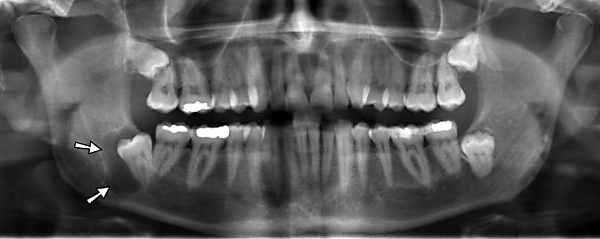

Ортопантомография (от греч.: orthos — прямой, правильный, pan — всё, tomos — ломоть, отрезанный кусок и grapho — писать, рисовать) — особый вид рентгеновской съёмки костей лицевого скелета, при котором они «развёртываются» в одну плоскость[1]. Другими словами рентгенологическое исследование в стоматологии, челюстно-лицевой хирургии, косметологии, позволяющее получать развёрнутое изображение всех зубов с челюстями, прилежащими отделами лицевого скелета. Является первичным рентгенологическим исследованием[2].

3. Костей челюстей и прилежащего лицевого скелета. Переломы (травматические, патологические) костей челюсти и лицевого скелета, новообразования, воспалительные процессы (остеомиелит, периостит), состояние полостей в костях (околоносовых пазух) и пр.

Галерея